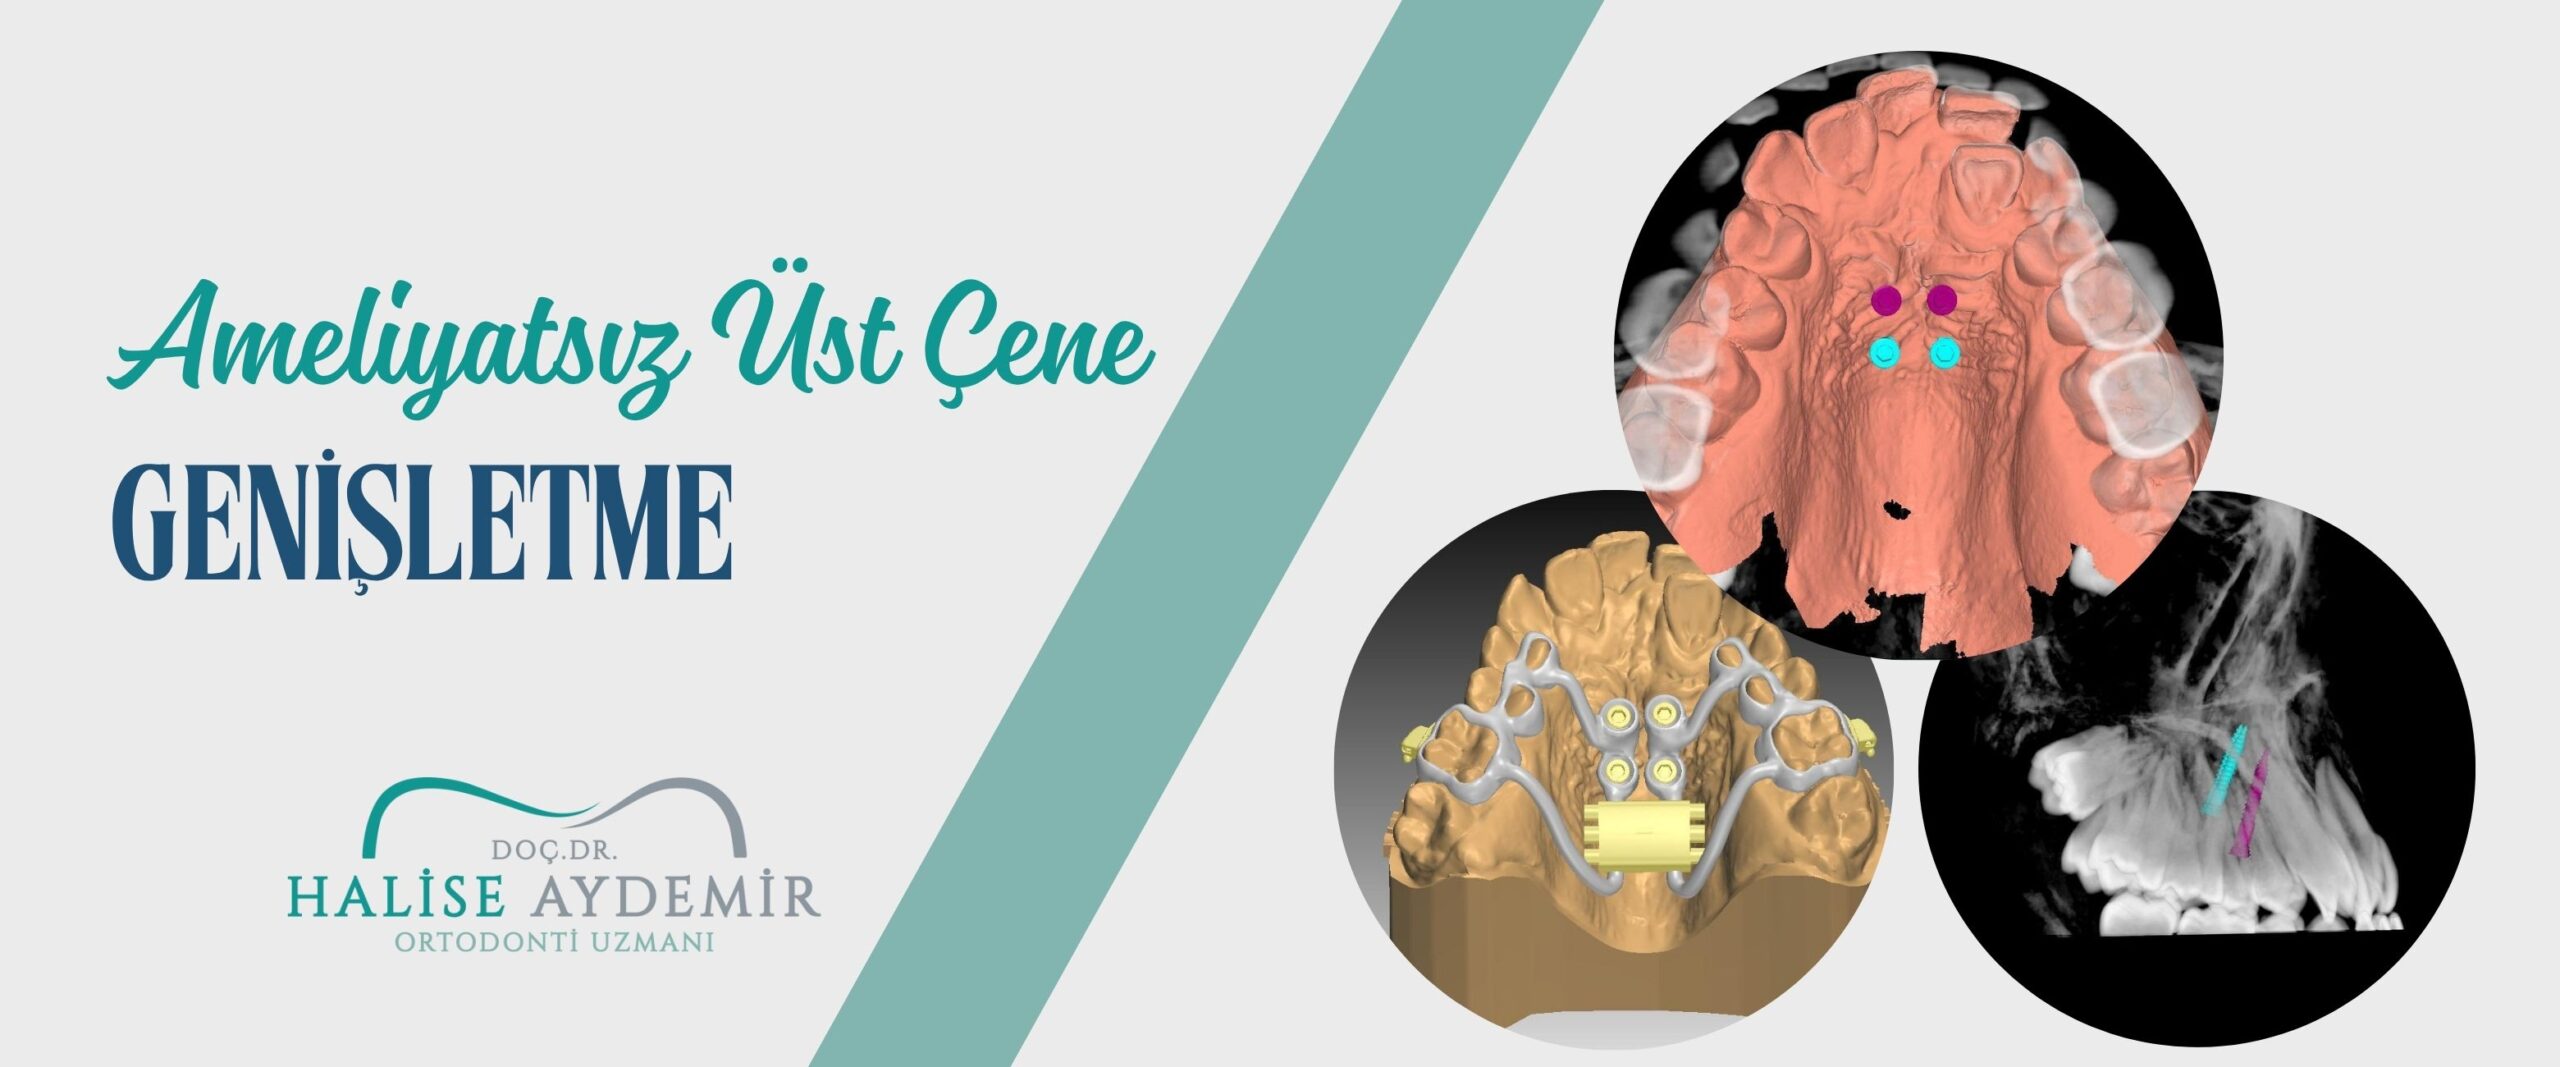

Uzmanlık sonrasında özellikle ortognatik cerrahi, damak-dudak yarıkları, çeşitli sendromlar, Sınıf II ve Sınıf III maloklüzyonlar, açık kapanış (open bite) ve derin kapanış (deep bite) gibi kompleks vakalar üzerine yoğunlaşarak 2018 yılında doçentlik unvanını almıştır.

Doç. Dr. Halise Aydemir hastalarına en güvenilir ve en güncel tedavi yöntemlerini sunarak, çene yapısını en sağlıklı ve doğal haline getirmeyi amaçlamaktadır. Düzelen çene ve diş yapısıyla birlikte daha iyi bir nefes alma fonksiyonu, daha iyi konuşabilme (fonasyon), daha düzgün bir yüz simetrisi, daha güçlü bir çene yapısı, daha sağlıklı çene eklemi ve çiğneme fonksiyonuna sahip olabilirsiniz.